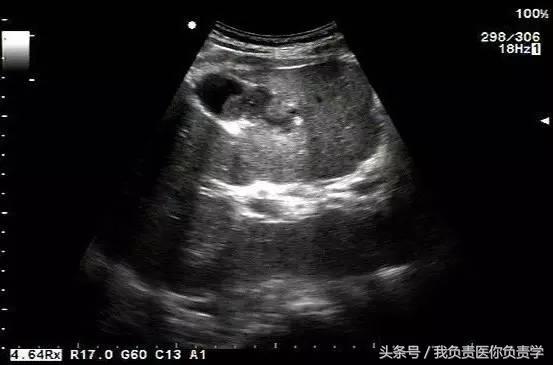

典型病例 1

患者男,64岁,因右上腹疼痛半月余就诊。查体发现右上腹部轻压痛,无发热。超声检查所见如下:

图3示胆囊与囊性回声区间隐约可见裂隙相通

图4和5为局部放大图像,可见胆囊与囊性回声区间可见直径约2mm的通道

超声检查考虑为胆囊炎合并胆囊穿孔,后经CT检查证实。